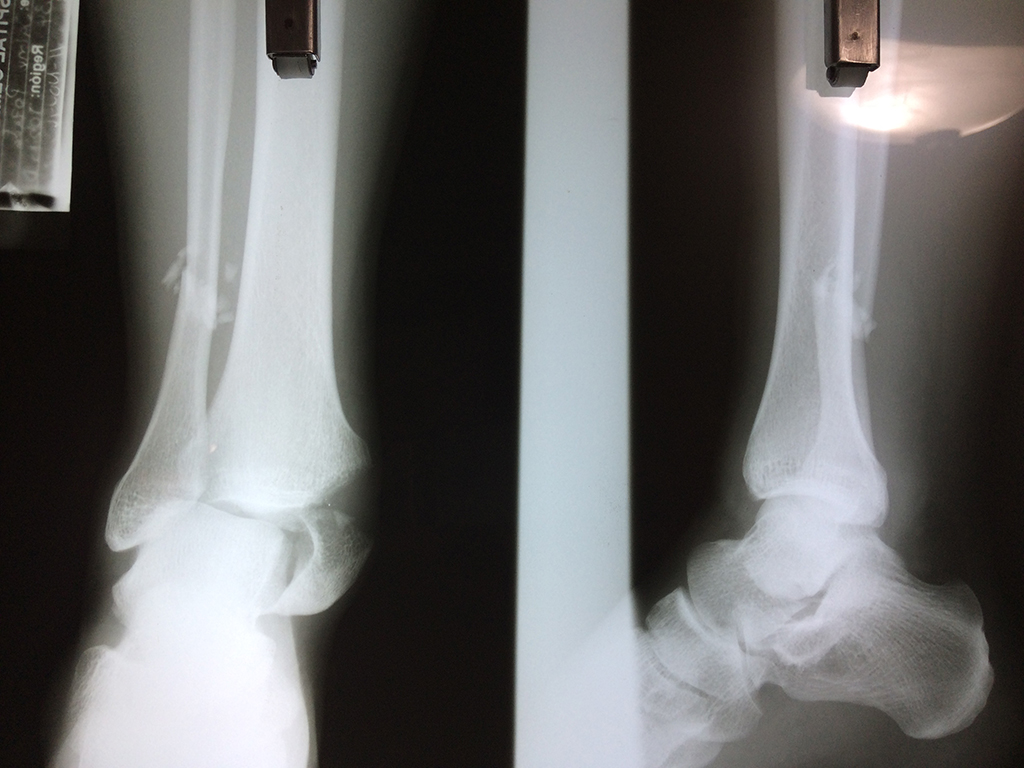

Cuando se necesita cirugía, es probable que esta implique el uso de clavijas de metal, tornillos o placas para sostener los huesos en su lugar mientras la fractura se consolida. Los elementos de soporte pueden ser temporales o permanentes.